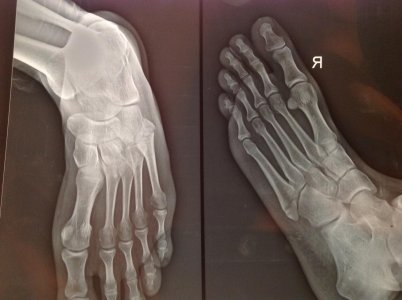

Здравствуйте! Я нахожусь сейчас за границей, в Индии. 28 марта упал с байка и перелом 5-й плюсневой кости. Снимок сделал в этот же день, нога была опухшая и 5 дней я ходил в повязке, 2 апреля мне наложили гипс и сказали носить его три недели, на ногу можно будет чуть-чуть наступать спустя неделю. После снятия гипса, два-три дня продолжать ходить на костылях, потом можно просто начинать полноценно ходить.

Спустя 11 дней после падения сделал повторный снимок когда уже был в гипсе.

Хотел спросить у Вас, все ли верно сказал доктор?

Вложения

• image.jpg

image.jpg

174,5 КБ · Просмотры: 1 127

223,6 КБ · Просмотры: 828

При данном переломе гипсовая иммобилизация должна составлять 4-5 недель.